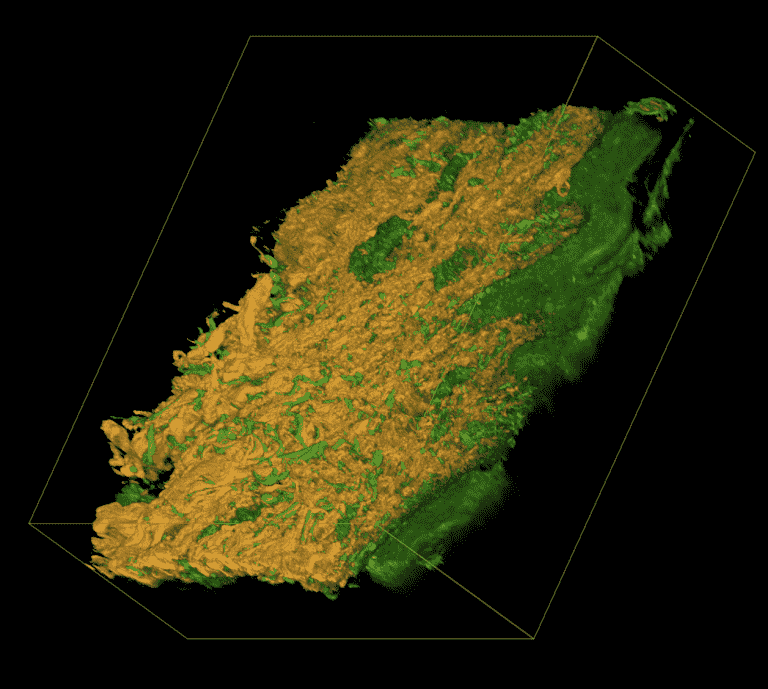

Das chronische Lymphödem ist eine Erkrankung des Lymphgefäßsystems, bei der es zu einer Ansammlung von Lymphflüssigkeit im Gewebe kommt. Die entsprechende Region schwillt an und die Patienten sind kosmetisch aber auch funktionell stark eingeschränkt. Der Goldstandard weltweit ist weiterhin die konservative Therapie (komplexe physikalische Entstauungstherapie). Zu den derzeit bedeutendsten chirurgischen Therapieformen zählt die mikrochirurgische Lymphknotentransplantation, die vor allem in den letzten 10 Jahren zunehmend an Popularität gewinnt. Dabei wird von der gesunden Seite ein Lymphknotenpaket entnommen und dieses mikrochirurgisch in der erkrankten Region an ein Empfängergefäß angeschlossen. Ein wesentlicher Nachteil dieser Technik ist jedoch die lange OP-Zeit von bis zu 5 Stunden und das Risiko ein neues Lymphödem an der Entnahmestelle zu verursachen.

Unser Forschungsziel ist es ein neues innovatives Verfahren zu etablieren, die sog. Bioartifiziellen Lymphknoten. Dabei werden gezielt nur 1 oder 2 Lymphknoten entnommen, mechanisch zerkleinert und auf PCL Scaffolds mit biologischem Gel fixiert. Diese werden dann in derselben Sitzung in die erkrankte Region transplantiert ohne Mikrochirurgie. Die Lymphknoten regenerieren und es kommt zur einer Neubildung von Lymphgefäßen.

Durch diese Technik verkürzt sich die OP-Zeit wesentlich und das Risiko ein neues Lymphödem auf der gesunden Seite zu verursachen wird deutlich verringert. Erste Tierversuche in Mäusen und Minischweinen zeigen bereits das hohe Regenerationspotenzial von Lymphknotengewebe und erste Hinweise für Lymphgefäßneubildung.